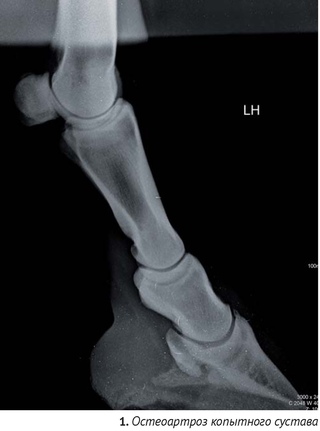

Артроз суставов у собаки

Артроз суставов у собаки 141 фотографий